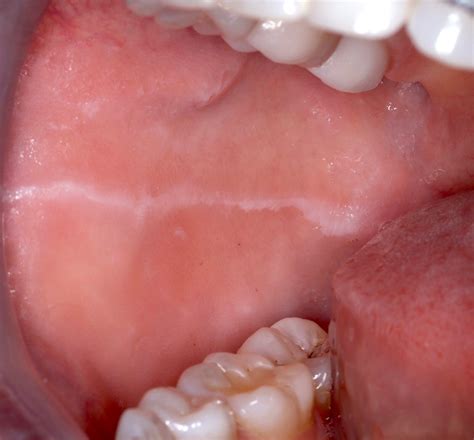

Cheek Linea Alba

Characteristics of the Cheek Linea Alba

The Cheek Linea Alba has several distinct characteristics that help in its identification:

• Appearance: The line is typically white or light-colored and can vary in thickness and length. It often appears on the cheeks, near the nasolabial folds.

• Location: The Cheek Linea Alba is usually found on the cheeks, but it can also appear on other parts of the face, such as the forehead or chin.

Cheek Linea Alba Image